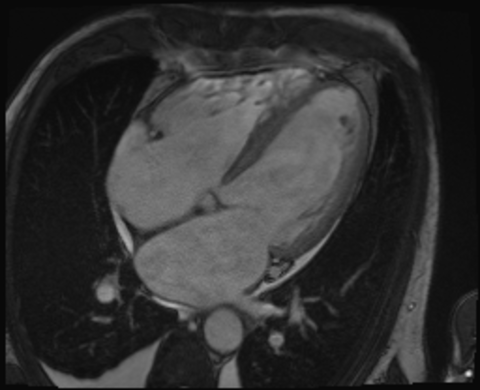

Die MRT bietet die Möglichkeit die Anatomie des Herzens, die Funktion der Herzkammern und die Morphologie des Herzmuskels detailliert darzustellen. Dazu arbeitet die Methode ohne Röntgenstrahlen. Die Untersuchung findet in einer großen Röhre statt (Durchmesser ca. 70 cm), zudem weht ein leichter "Wind", so dass die meisten Patienten kein Engegefühl empfinden. Je nach Fragestellung dauert die Untersuchung ca. 45 min, dazu kommt die Zeit zum Lagern, so dass wir insgesamt mit ca. 60 min planen.

Mittels kardialer Magnetresonanztomographie (MRT) kann die Größe und Funktion des Herzens gemessen sowie Erkrankungen des Herzmuskels oder der Herzklappen genau charakterisiert werden. Des Weiteren ist die kardiale MRT die Methode der Wahl zur genauen Diagnose und Nachsorge bei angeborenen Herzfehlern. Da bei einer MRT-Untersuchung nur Magnetfelder und Radiowellen zum Einsatz kommen, sind Nebenwirkungen durch ionisierende Strahlen wie bei herkömmlichen Röntgenuntersuchungen ausgeschlossen.